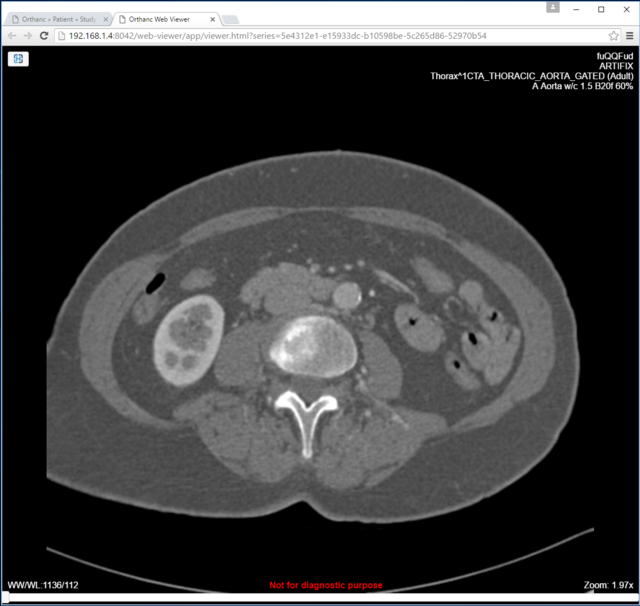

4. Orthanc Web Viewer example image

3. Orthanc DICOM server for medical imaging

- 1 x Orthanc PACS Server, installed on Ubuntu 16

- 1 x OrthancPi PACS Server, installed on Raspbian